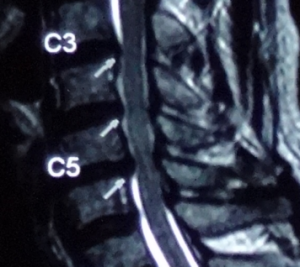

The most common cervical joints that are compressed on the cervical intervertebral disc are the fifth and sixth cervical vertebrae (C5, 6). Generally, X-rays show that the space between the vertebrae is reduced and the vertebrae have signs of degeneration. In addition to the fifth and sixth cervical vertebrae, there are also third and fourth cervical vertebrae (C3, 4), which are also parts of greater compression, and the changes in other vertebrae will follow.

The pain and paralysis of each cervical disc herniation can be distributed in different area of the hand (Figure 1). To distinguish where the intervertebral disc is herniated, it is necessary to check the arm muscle strength in, perform reflex nerve tests, and notice with the patient’s symptoms in order to confirm the diagnosis. Surgery cannot be made solely on the report of magnetic resonance (MRI). Magnetic resonance is to help doctors to confirm the diagnosis, not to help doctors diagnose the disease.